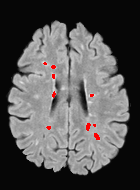

Patch size is another important parameter of the network. In computer vision applications such as object detection, usually a whole 2D image is used as a feature. However, full 3D medical images can not typically be used because of memory limitations. Fig. 4 shows examples of lesion memberships obtained with different sized 2D patches. As the patch sizes increases, the false positives that are mostly observed in the cortex tend to decrease. Fig. 5 shows a plot of Dice and LFPR with various patch sizes, ordered from left to right according to their increasing size. Note that smaller patches ( to ) produced significantly lower Dice and higher LFPR compared to other patches (), as seen from the memberships in Fig. 4. Also some of the highest Dice and lowest LFPR were observed for patches with large in-plane size, i.e., , , and . It was observed in Fig. 5 that there is no significant difference between Dice coefficients for , , or , but LFPR of both and are significantly lower than that of (). We chose as the optimal patch size. Other choices of smaller and patches (not shown) yielded worse results. Note that although training was performed with different patch sizes, the memberships were generated slice by slice, as the trained model consisted only of convolutions and did not need any information about patch sizes.

In our experiments, we used large 2D patches similar to Ghafoorian et al. (2017b), in comparison to isotropic 3D patches as used before, e.g., in Valverde et al. (2017), in Wachinger et al. (2017), and in Kamnitsas et al. (2017). The rationale behind using large anisotropic patches is twofold. First, experiments with full 3D isotropic or patches showed little or no improvement in Dice and led to increased false positives, with memberships similar to the one with patches, as shown in Fig. 4. Larger isotropic patches, e.g. or , showed inferior segmentation, and in some cases, optimization did not converge. The reason is that the FLAIR images in the test datasets had inherently low resolution in the inferior-superior direction, mm and mm compared to in-plane resolution of mm. Therefore 2D axial patches capture the high resolution in-plane information that represents the original thick axial slices. Second, the lesions are usually focal and small in size, unlike other brain structures. Therefore a very large isotropic patch around a small lesion can include superfluous information about the lesion, which can increase the amount of false positives. Note that with in more recent studies employing high resolution 3D FLAIR sequences, it is trivial to extend the algorithm to accommodate for 3D patches.